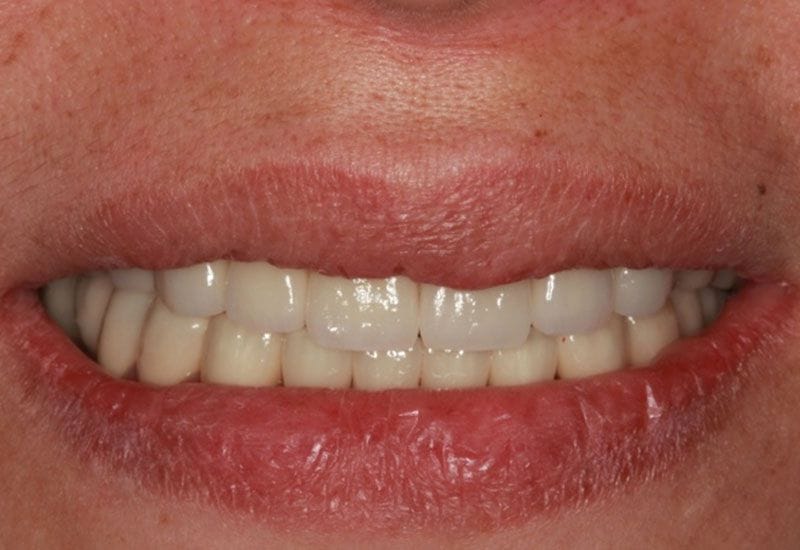

假牙完成後 病患恢復咬合功能,微笑曲線的建立與全瓷假牙的治療,讓病患有自信的笑容,牙齒也因為有了保護而減低敏感度,此後建議病患定期回診 並已製作咬合板 請病患於睡覺時配戴 防止夜間磨牙的高咬合力量造成假牙或牙齒的損害

如圖13.14

圖13

圖14